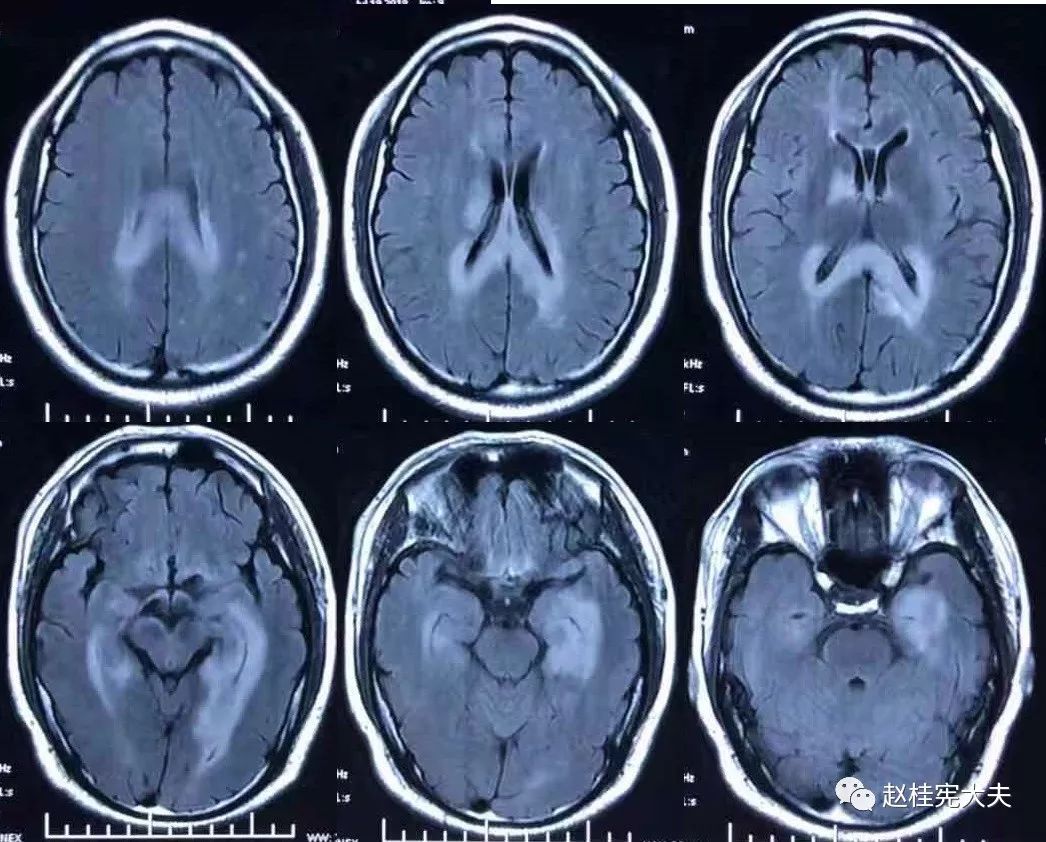

2018.7.6头颅MRI:胼胝体、穹隆及双侧脑室旁、基底节区、右侧延髓、桥臂异常信号,脱髓鞘病变考虑。头颅MRS:左枕叶病变区MRS显示:NAA下降,Cho升高,Cho/NAA=3.86,并见倒置乳酸峰。

2018.7.10磁共振增强:脑室周边病灶轻度强化。

7.20复查头颅MRI平扫:胼胝体、穹隆及双侧脑室旁、基底节区、右侧延髓、桥臂广泛信号异常,对照前片(7.10)范围明显缩小。

2018.10复查头颅MRI:胼胝体压部、左侧部分枕颞叶、侧脑室枕角旁、中脑脱髓鞘病变,视神经脊髓炎谱系病?结合对照前片(7.4)病变范围有所缩小。

我看到患者时的思考:当了解了患者前期诊疗经过后,在看到患者磁共振片子时,我的第一反应就是淋巴瘤。尽管患者激素治疗后症状有好转,病灶在磁共振上看起来也是有好转,但淋巴瘤也会出现这样的表现。

我对满脑室边的病灶的体会是:遇到这样的病例,首先要考虑感染、肿瘤(如室管膜瘤、生殖细胞瘤、淋巴瘤或转移瘤脑室播散等等),炎症要放到后面去考虑,脱髓鞘的诊断要打个大大大大的?。炎症中,血管炎不像,自免脑也不是很支持,尽管边缘系统似乎也有受累,但患者边缘叶脑炎的精神、行为异常、癫痫等症状很少,而且磁共振上看去除了边缘系统,整个脑室系统都有受累,这个和常见自免脑不符。视神经脊髓炎谱系病?尽管病灶在水通道蛋白富集区,但这样的视神经脊髓炎(视神经和脊髓均未受累,近脑室边的异常信号)至少罕见,即使诊断,也应该是排除其它的疾病后才可能考虑。

患者住院期间还请眼科会诊,除双眼玻璃体轻度浑浊,视力、视野、OCT均未见明显异常,未建议行玻切明确诊断。患者入院后嗜睡症状有加中,但一直未诉头痛,仅是头昏,静滴甘露醇症状减轻不明显。复查头颅磁共振平扫+增强:病灶范围较前明显扩大。轻度强化。